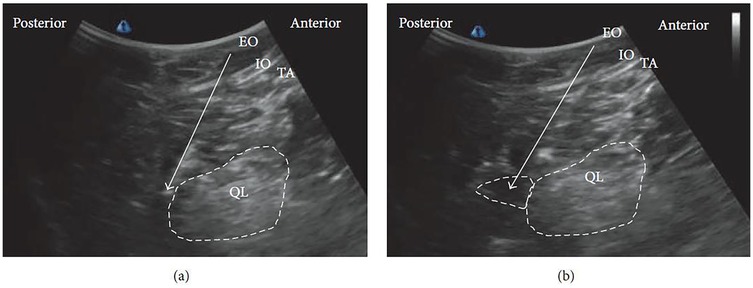

In clinical practice, a curvilinear ultrasound probe (2–6 MHz) is most frequently used; however, in thinner patients, a linear probe may be sufficient. When the probe is positioned transversely above the iliac crest, the characteristic “shamrock sign” becomes visible, serving as a key sonographic landmark (Figure 2) (3436).

Ultrasound image showing labels of muscle groups and structures. From left to right: PC (Psoas Major Muscle), PM (Psoas Major), QL (Quadratus Lumborum), TP (Transverse Process), ES (Erector Spinae). Anterior and posterior orientations are marked.

Figure 2. The “shamrock sign” obtained with a curvilinear ultrasound probe. ES, erector spinae muscle; L4, fourth lumbar vertebra; PC, peritoneal cavity; PM, psoas muscle; QL, quadratus lumborum muscle; TP, transverse process [Reproduced from Nee and McDonnell (35). © 2025 World Federation of Societies of Anaesthesiologists. Distributed under the Creative Commons Attribution License, CC BY 4.0].